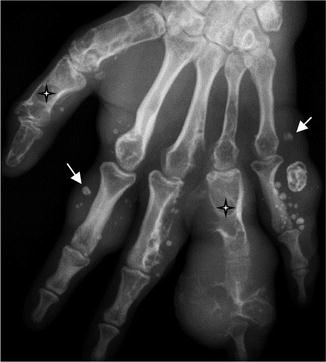

Maffuci syndrome. Plain radiograph of the hand. Multiple, expansible, well-defined and predominantly lytic lesions within the phalanges and metacarpals of the hand (stars) correspond to multiple enchondromas. The presence of phleboliths (arrows) within the soft tissue are highly suggestive of a Maffuci syndrome